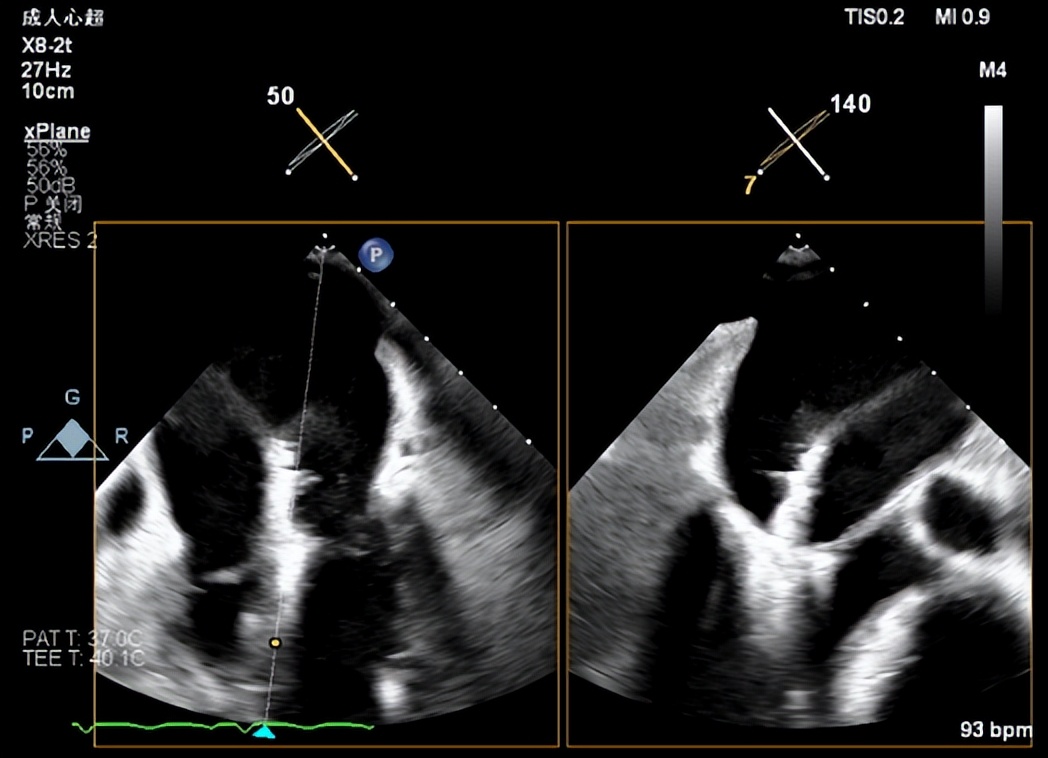

全麻状态下陈魁主任手术团队(图四)经右侧股静脉穿刺,通过MitraClip®独特的三层双调弯设计,经房间隔穿刺顺利将导管送入左心房和左心室,到达二尖瓣膜目标位置调整角度抓取瓣叶(图五)。随后,术者精准对位释放MitraClip®夹合器,准确捕获并固定(图六),“缘对缘”技术使二尖瓣由大的单孔变成小的双孔,位置精确(图七)控制返流且无瓣口狭窄(图八),血流动力学明显改善,手术取得圆满成功。

图五(瓣下调整角度并成功夹取瓣叶)

图六(MitraClip关闭双臂,稳定地固定住瓣叶)